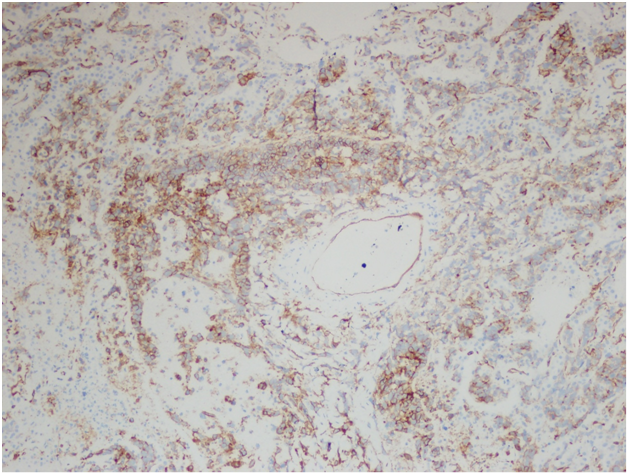

However, the wedge resection of the right lower lobe revealed angiosarcoma with lymphovascular invasion. This biopsy showed highly atypical and large malignant cells with increased mitoses (Figure 2A&2B). The immunohistochemical stains showed diffuse positivity for CD31, CD34, and vimentin (Figures 3A-3C). Stains for AE1/AE3 (Figure 3D), cam5.2, TTF-1, desmin, and OCT3/4 were negative. Along with the clinical history, a final diagnosis of angiosarcoma of the heart with metastases to the lungs was made.

Figure 3A Right lower lobe wedge resection. Immunohistochemical stain for CD31, 400x.

Figure 3B Right lower lobe wedge resection. Immunohistochemical stain for CD34, 400x.

Figure 3C Right lower lobe wedge resection. Immunohistochemical stain for vimentin, 400x.

Figure 3D Right lower lobe wedge resection. Immunohistochemical stain for AE1/AE3, 400x.